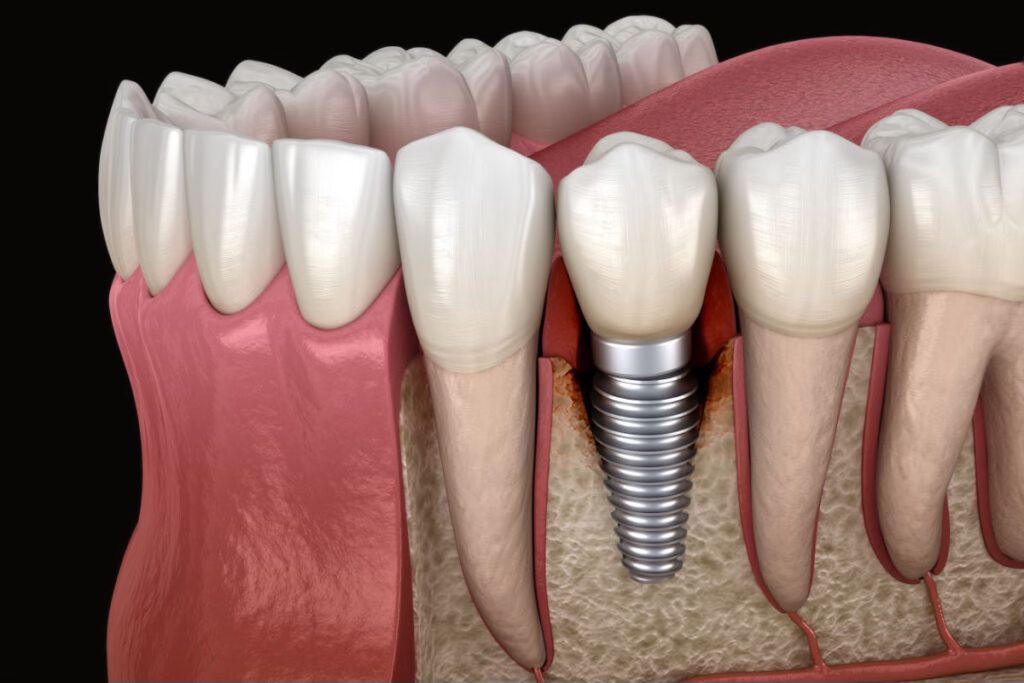

Oral Implantology

•Dental implants (Straumann)

Dental implants have gained popularity due to their high success rate, but not all offer the same quality. At BioDental Clinic, we work with Straumann implants, ensuring durability, safety, and optimal long-term results.